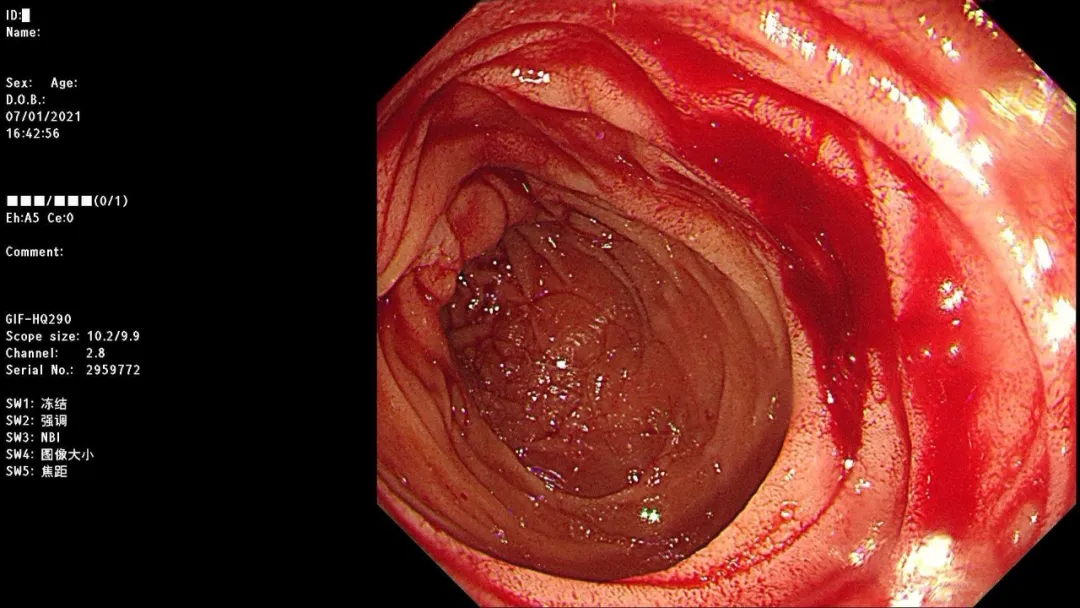

急诊胃镜示:小弯近胃窦侧活动性出血灶活动性渗血,采用OTSC吻合夹予以夹闭治疗,检查诊断:胃窦杜氏溃疡并出血OTSC吻合夹夹闭止血治疗术。